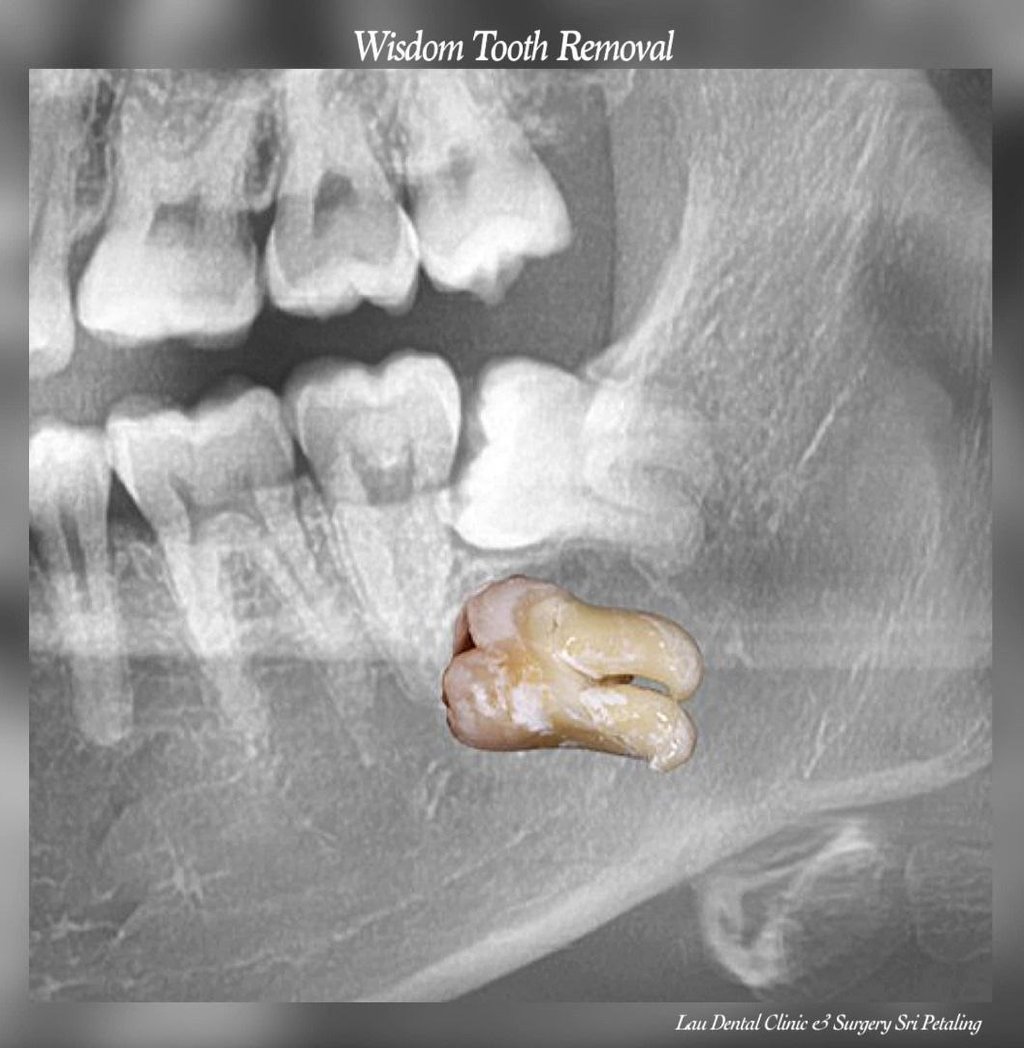

Minor Oral Surgery (MOS) is a routine dental procedure used to treat conditions such as impacted wisdom teeth, broken tooth roots, or oral infections that require more than standard dental care.

Minor Oral Surgery involves small surgical procedures done inside the mouth, often under local anaesthesia. The most common reason patients need MOS is to remove impacted or partially erupted wisdom teeth. However, it’s also used for removing broken tooth roots, treating dental cysts, or even preparing the mouth for dentures or implants. Unlike major surgery, MOS is minimally invasive, doesn’t require general anaesthesia, and is usually completed in under two hours.

At Lau Dental Clinic & Surgery, the process begins with a thorough consultation and digital X-ray, all done in-house. This allows us to assess your condition on the spot — and in many cases, proceed with treatment on the same day.

Once you're comfortable and the area is numb, our experienced dentist gently makes a small incision to access the tooth or problem area. Depending on the complexity, the tooth may be removed whole or in smaller sections. The site is then cleaned and stitched if necessary. Most MOS procedures here take only about 1 to 1.5 hours, and patients are often surprised by how quick and painless it feels.